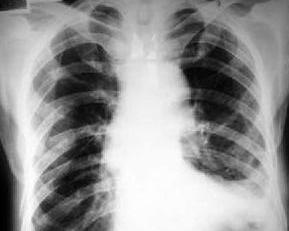

肋骨共12对,平分在胸部两侧,前与胸骨、后与胸椎相连,构成一个完整的脚廓。胸部损伤时,无论是闭合性损伤或开放性损伤,肋骨骨折最为常见,约占胸廓骨折的90%。不同的外界暴力作用方式所造成的肋骨骨折病变可具有不同的特点:作用于胸部局限部位的直接暴力所引起的肋骨骨折,断端向内移位,可刺破肋间血管、胸膜和肺,产生血胸或(和)气胸,间接暴力如胸部受到前后挤压时,骨折多在肋骨中段,断端向外移位,刺伤胸壁软组织,产生胸壁血肿。枪弹伤或弹片伤所致肋骨骨折常为粉碎性骨折,在儿童,肋骨富有弹性,不易折断,而在成人,尤其是老年人,肋骨弹性减弱,容易骨折。